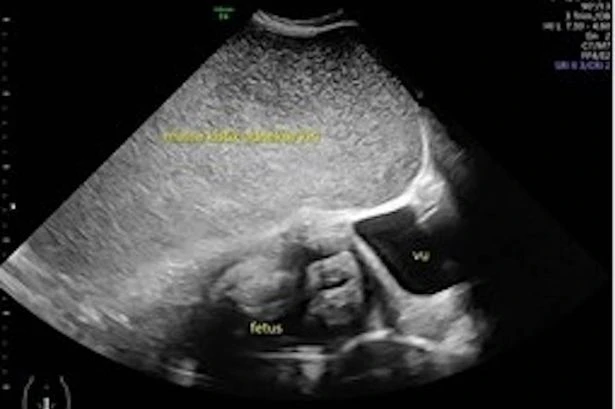

Pregnant woman complains of tummy pain before ultrasound scan unveils alarming find